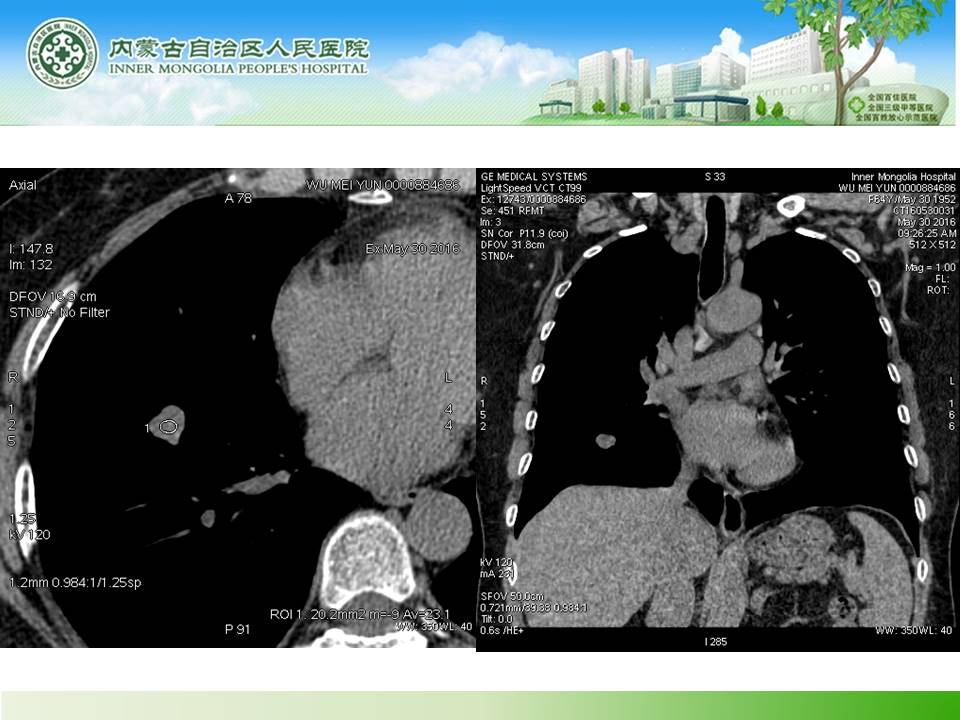

右肺下叶硬化性血管瘤1例CT